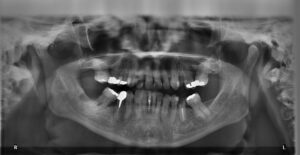

At your first visit with Broomfield Dental Care you will more than likely have some x-rays of your teeth. This is important because it gives a detail look at your oral care, and your dentist will be able to diagnose any issues that may be occurring in your mouth.

X-rays are used for a variety of reasons when it comes to dental work. It can help your dentists detect damage, disease or cavities. Typically, x-rays are a part of a routine dental visit. However, rather or not an x-ray should be taken will depend on an individual’s oral health, age, risk for disease, and signs of oral disease.